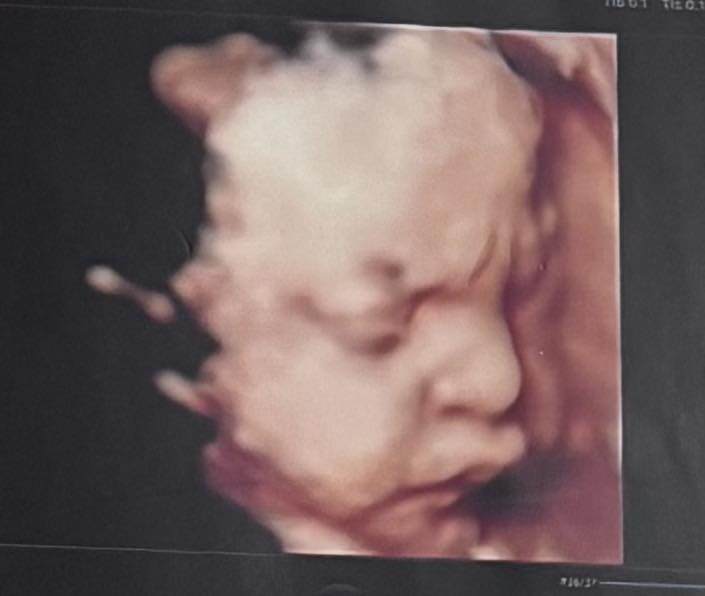

Mới đây, quán quân The New Mentor 2023 tiếp tục gây chú ý khi chia sẻ ảnh siêu âm cận mặt em bé. Ngay lập tức, khán giả dành sự quan tâm lớn cho “bản sao nhí” của người đẹp Hà Nội.

Lê Thu Trang chia sẻ ảnh siêu âm cận mặt thai nhi.

Trong bài đăng trên trang cá nhân, Thu Trang khiến dân mạng thích thú khi khoe ảnh siêu âm rõ nét của con, đồng thời tiết lộ tên thân mật của bé là Bamboo. Cận mặt của nhóc tỳ được nhận xét có nhiều nét giống mẹ, đặc biệt là sống mũi cao thẳng và đôi môi chúm chím. Đông đảo khán giả và bạn bè đồng nghiệp để lại bình luận: “Đúng là bản sao nhí của mẹ rồi”; “Trộm vía, nhìn mũi với môi như photocopy từ Thu Trang”; “Sao chưa chào đời mà đã chiếm spotlight thế này”...

Trong khi đó, ông xã Thu Trang cũng không giấu được sự bất ngờ, hài hước viết: “Góc cầu cứu, siêu âm hình thái xong thấy con mình không giống mình, vậy phải làm sao đây các anh em hội sợ vợ?”.

Câu nói này ngay lập tức khiến cư dân mạng bật cười. Bởi trước đó, nam diễn viên từng thú nhận mình chính thức gia nhập “hội sợ vợ” sau ngày cưới. Giờ lại sắp chào đón thêm một phiên bản nhí giống hệt vợ, dân tình càng thêm trêu chọc, lo lắng cho anh chàng trong tương lai.